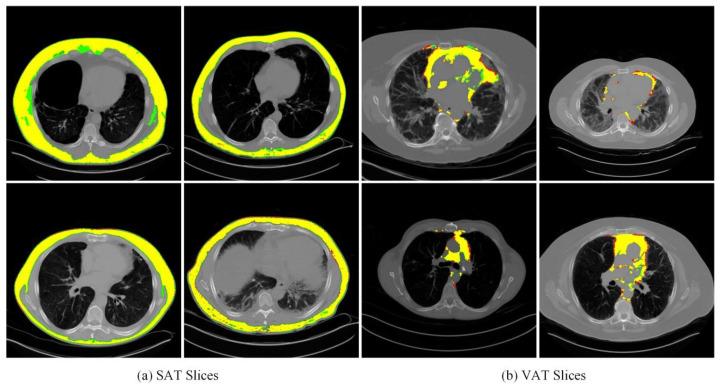

Adipose Tissue Segmentation after Lung Slice Localization in Chest CT Images Based on ConvBiGRU and Multi-Module UNet.

The distribution of adipose tissue in the lungs is intricately linked to a variety of lung diseases, including asthma, chronic obstructive pulmonary disease (COPD), and lung cancer. Accurate detection and quantitative analysis of subcutaneous and visceral adipose tissue surrounding the lungs are essential for effectively diagnosing and managing these diseases. However, there remains a noticeable scarcity of studies focusing on adipose tissue within the lungs on a global scale. Thus, this paper introduces a ConvBiGRU model for localizing lung slices and a multi-module UNet-based model for segmenting subcutaneous adipose tissue (SAT) and visceral adipose tissue (VAT), contributing to the analysis of lung adipose tissue and the auxiliary diagnosis of lung diseases. In this study, we propose a bidirectional gated recurrent unit (BiGRU) structure for precise lung slice localization and a modified multi-module UNet model for accurate SAT and VAT segmentations, incorporating an additive weight penalty term for model refinement. For segmentation, we integrate attention, competition, and multi-resolution mechanisms within the UNet architecture to optimize performance and conduct a comparative analysis of its impact on SAT and VAT. The proposed model achieves satisfactory results across multiple performance metrics, including the Dice Score (92.0% for SAT and 82.7% for VAT), F1 Score (82.2% for SAT and 78.8% for VAT), Precision (96.7% for SAT and 78.9% for VAT), and Recall (75.8% for SAT and 79.1% for VAT). Overall, the proposed localization and segmentation framework exhibits high accuracy and reliability, validating its potential application in computer-aided diagnosis (CAD) for medical tasks in this domain.